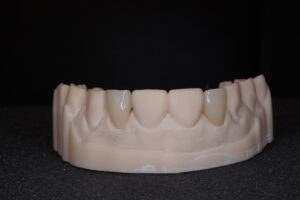

【技工物】

担当医:東 由紀子 カウンセリング:前田 夏葵 技工ラボ:シェイプデンタルアート様